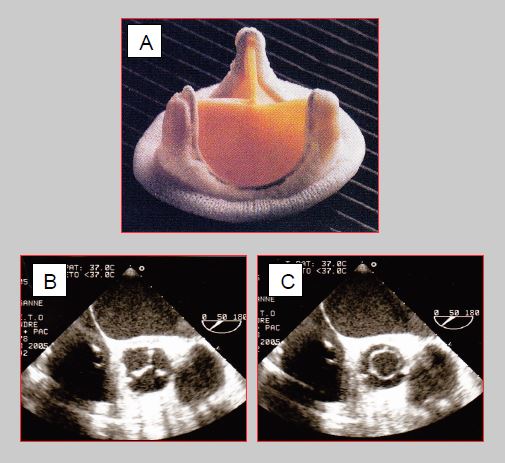

- Valve à double ailette (St.Jude Medical™, Carbomedics™, ATS™, On-X™) en titane et pyrolocarbone : lorsqu’elles ont ouvertes, les ailettes forment un angle de 85° avec le flux, qui passe par 2 orifices en demi-lune de chaque côté et par un petit orifice central de section rectangulaire où le gradient est plus important. En position fermée, les ailettes font un angle de 25-30° avec le plan de l’anneau et présentent de petites fuites sur les bords (jonction ailette – anneau) et au niveau des pivots (Figure 11.36). La prothèse On-X™, faite en pyrolocarbone sans alliage, se fixe en position supra-annulaire, ce qui permet de gagner une taille, soit 2 mm de diamètre. Le flux et le gradient se mesurent dans les deux orifices latéraux et non dans le petit orifice central, où le gradient est jusqu’à 40-50% plus élevé [43,47]. Ces prothèses ont une durée de vie d’au-moins 25 ans (Vidéo).

Figure 11.36 : Valve à double ailette (St.Jude Medical™, Carbomedics™, ATS™). A : valve mécanique bi-ailette (Extrait de: Zipes DP et al, eds. Braunwald's Heart disease, 7th ed. Philadelphia:Elsevier Saunders, 2005. Figure 57.47). B : schéma et image ETO d’une valve bi-ailette ouverte en position mitrale. Lorsqu’elles ont ouvertes, les ailettes forment un angle de 85° avec le flux, qui passe par 2 orifices en demi-lune de chaque côté et par une fente centrale de section rectangulaire où le gradient est plus important. C : schéma et image ETO d’une valve bi-ailette fermée en position mitrale. En position fermée, les ailettes font un angle de 25° avec le plan de l’anneau et présentent des fuites d’autolavage sur les bords et au niveau des pivots. La prothèse est mise en place avec ses ailettes en position anti-anatomique par rapport aux feuillets de la valve mitrale, raison pour laquelle le profil dans lequel on voit les deux ailettes est situé entre 30° et 80° à l’ETO.